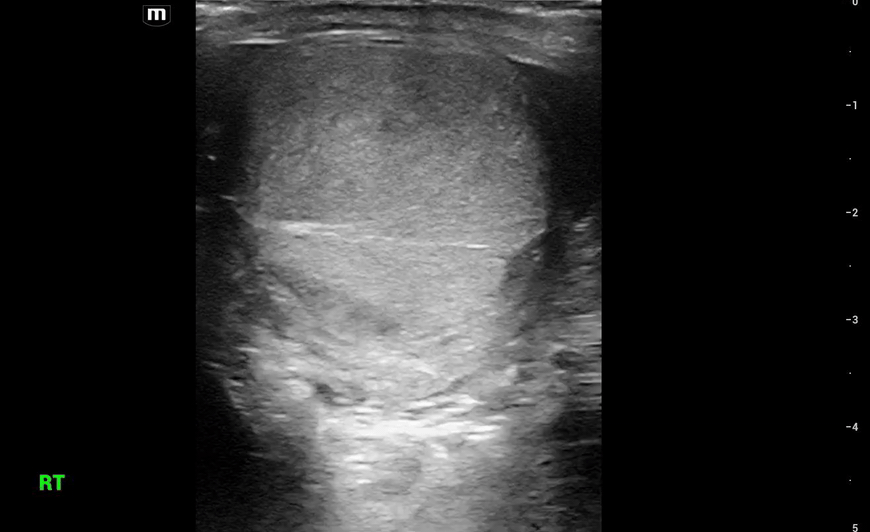

This is what we see:

Right Testicle is shown above.

• Notice how the echotexture of the testicle is not homogenous all the way through, which should catch your eye as a potential abnormal finding.

• It is important to also note that the anechoic area to the R of the screen can be hematocele, abscess (less likely), varicocele, or hydrocele. Clinical context is very important to making the correct diagnosis with ultrasound.

The main sign of testicular rupture on ultrasound is irregular testicular contour, extrusion of testicular contents, or heterogeneity of the testicular tissue.

Other findings can include a hematocele. A hematocele is a collection of blood within the tunica vaginalis. While not diagnostic of rupture alone, a large hematocele is highly suspicious for underlying testicular injury.